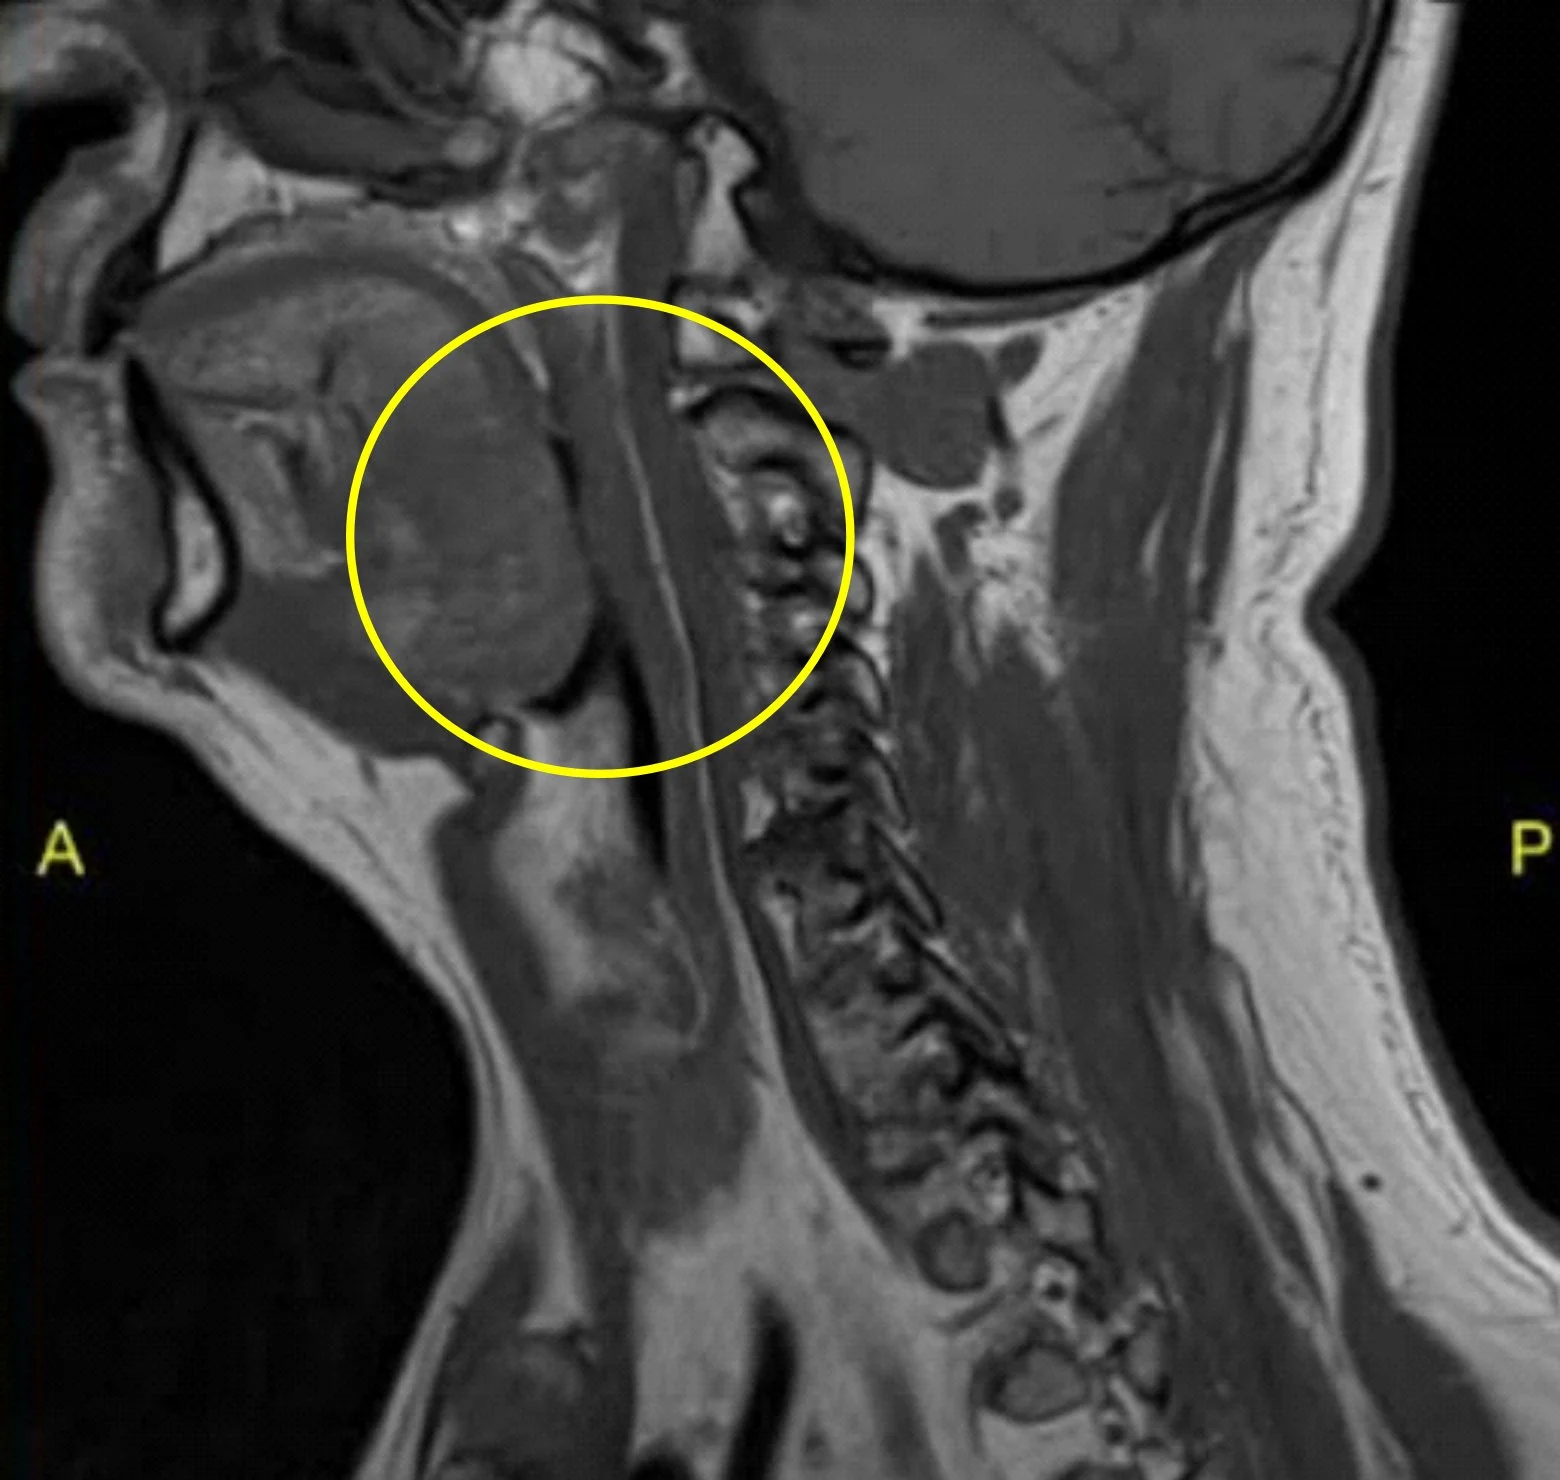

MRI SCAN BEFORE APNEACURE

Tongue Obstructed Airway

Chronic OSA